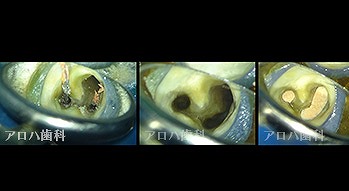

破折器具除去症例

case6

破折器具の除去 麻痺の恐れ

case7

MB根 湾曲の先に破折器具

器具の除去